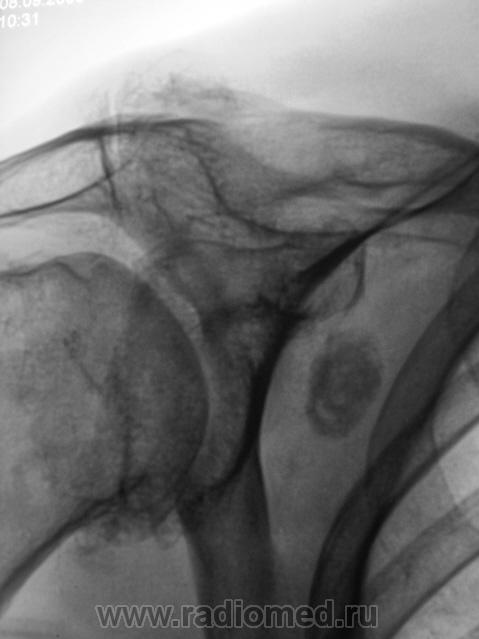

Пол пациента: Мужской пол Тип патологии: Доброкачественное новообразование, киста Область исследования: Скелетно-мышечная система Методы исследования: Rg При обследовании пациента - рентгенологическое исследование органов грудной полости выявлен "патологический процесс" лопатки. Ваше мнение коллеги? Thu, 10/09/2009 - 20:48 #1 tatyana Offline Last seen: 4 years 6 months ago Joined: 24.06.2009 - 08:33 Posts: 2090 если изменения в лопатке (а локализацию, я полагаю, Вы, Валентин Львович, уже установили при рентгеноскопии ) - хондрома или остеома; если в мягких тканях - хондромное тело или обызвествленный л/узел "самоуверенность дилетантов - предмет зависти профессионалов" Thu, 10/09/2009 - 21:05 #2 Катенёв Валенти... Offline Last seen: 7 years 5 months ago Joined: 22.03.2008 - 22:15 Posts: 54876 Образование интимно связано с лопаткой, проверил - поставил пациента за екран.

Образование интимно связано с лопаткой, проверил - поставил пациента за екран.